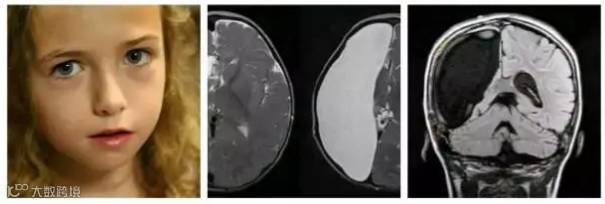

然而你们可能不知道有一种吓人的手术叫做“半脑切除术”,通过切除半个大脑来治疗严重癫痫和其他脑部疾病。这种手术已经有快一个世纪的历史了。

患者在手术后基本得到治愈,除了被切除脑部对侧的眼睛和手有些影响外,性格、智力、记忆和幽默感与常人无异。而且手术时年龄越小,差异就越小。(图1就是一个半脑人小姑娘,有兴趣可以搜搜看。)

人脑是可塑的,它和电脑不一样,并不像我们想象的那样有明确的功能分区。而事实上,有些人花了大半辈子,才发现自己的脑子里装的都是水;有人没了半个脑子照样活蹦乱跳着呢。。引用某位名人的话来说:“以大部分人的努力程度根本没有谈大脑潜力的资格。”